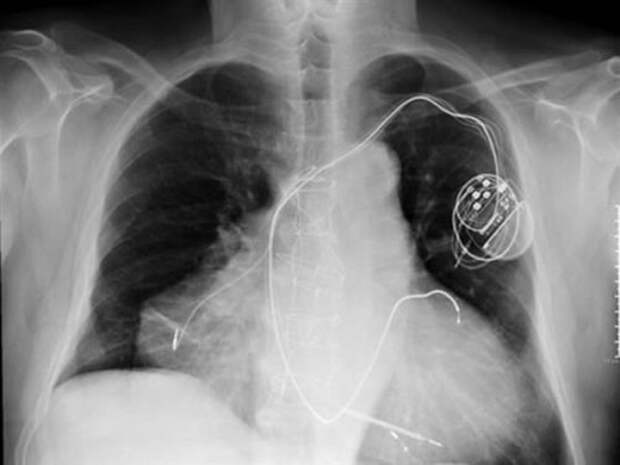

6. Человек с двумя сердцами, который перенёс двойной сердечный приступ

Поначалу казалось, что в человеке, который в 2010 году поступил в отделение неотложной помощи Вероны, Италия не было ничего необычного. Ему не хватало дыхания, он потел, и у него было низкое кровяное давление, что без сомнений указывало на сердечнососудистые проблемы. Врачи скорой помощи постоянно видят подобные симптомы.

Доктора думали, что они имеют дело с типичным случаем остановки сердца, пока они не изучили пациента более внимательно и не заметили его необычное состояние. Оказалось, что мужчина на самом деле не родился с двумя сердцами. Его второе сердце появилось после ранее сделанной медицинской процедуры проведённой на его изначальном сердце.

Процедура гетеротопическая трансплантации проводится для того, чтобы совместить новый, здоровый орган с поражённым. Конечно, существует неотъемлемый риск, что если пересадка пройдёт слишком хорошо у вас могут развиться два независимых сердечных ритма, особенно в сценарии, где состояние оригинального сердца немного улучшается. Судя по всему, именно это и случилось с итальянским пациентом. После того как он поступил в больницу врачи ввели ему лекарственную терапию в попытке исправить его нарушение ритма однако лекарство вызвало остановку обоих его сердец.

Затем врачи смогли успешно использовать дефибриллятор, чтобы одновременно реанимировать оба сердца. Сейчас он, как сообщается, чувствует себя хорошо с двумя своими функционирующими сердцами.